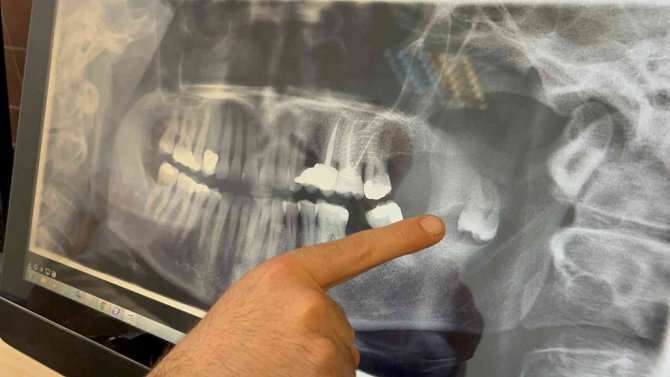

Süreç hakkında bilgi veren Doç. Dr. Ömür Dereci, hastanın yaklaşık birkaç ay önce çenesinde ciddi bir ağrı şikâyetiyle kliniğe başvurduğunu kaydetti. Doç. Dr. Dereci, "Yapılan incelemelerde çenesinde tamamen pozisyonu bozuk, ters dönmüş ve yukarı doğru çenenin derin taraflarına doğru ilerlemiş bir diş ve bu dişle ilişkili bir kiste rastladık. Cerrahi bir operasyonla hastamız tamamen uyutularak ameliyat edildi ve bu diş ve ilişkili kist buradan tamamen çıkarıldı. Yapılan muayene ve kontrollerde gayet iyi iyileştiği gözlendi" diye anlattı.

Sevan Kazak Ertural, yaklaşık 12 yıl önce bir panoramik röntgende fark ettikleri gömülü dişin çene kemiğindeki ramus bölgesinde yer aldığını söyledi. Bir zararı olmadığı ve riskli bölgede olduğu için bu dişi almaya kimsenin yanaşmadığını belirten Ertural, "Daha sonrasında dişin kistleştiğini ve çene kemiğime zarar verdiğini fark ettik. Çene kemiğimin bir kısmını eritmişti. Tekrar yaptığım başvurularımda kalıcı yüz felci olabileceğini, çenemin kırılabileceğini, sinire çok yakın olduğu için kolayca müdahale edilemeyeceğini söylediler. Bu sene içinde Ömür Hoca ile tanıştım, buraya başvurdum. Sağ olsun beni çok cesaretlendirdi, bütün riskleri anlattı. Korkmamam gerektiğini söyledi ve ondan güven alarak burada ameliyat olmaya karar verdim" dedi.